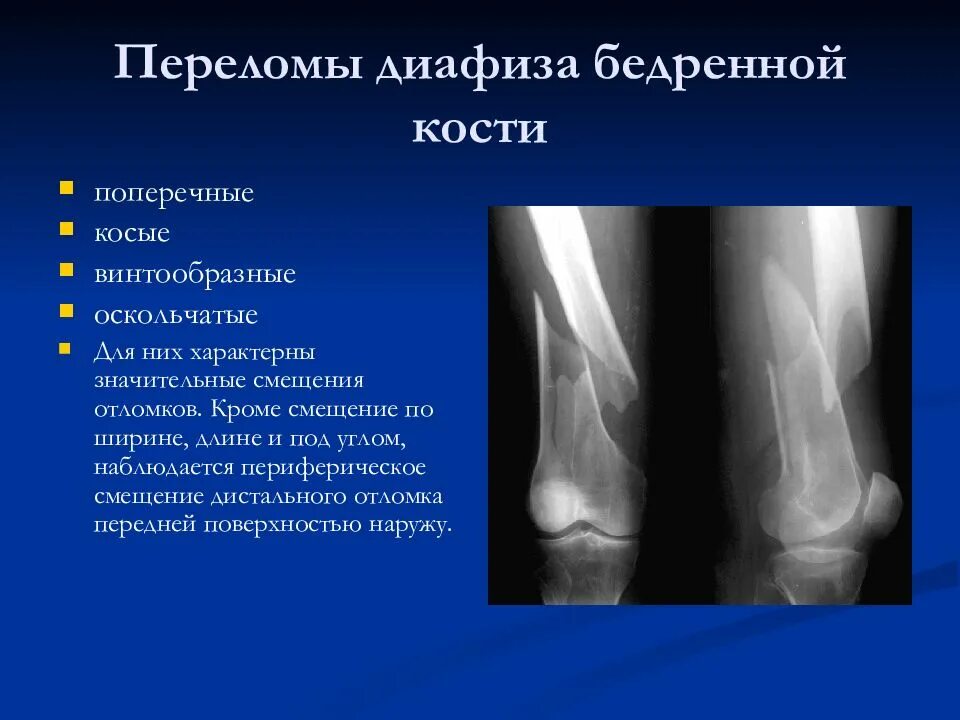

Укорочение трубчатых